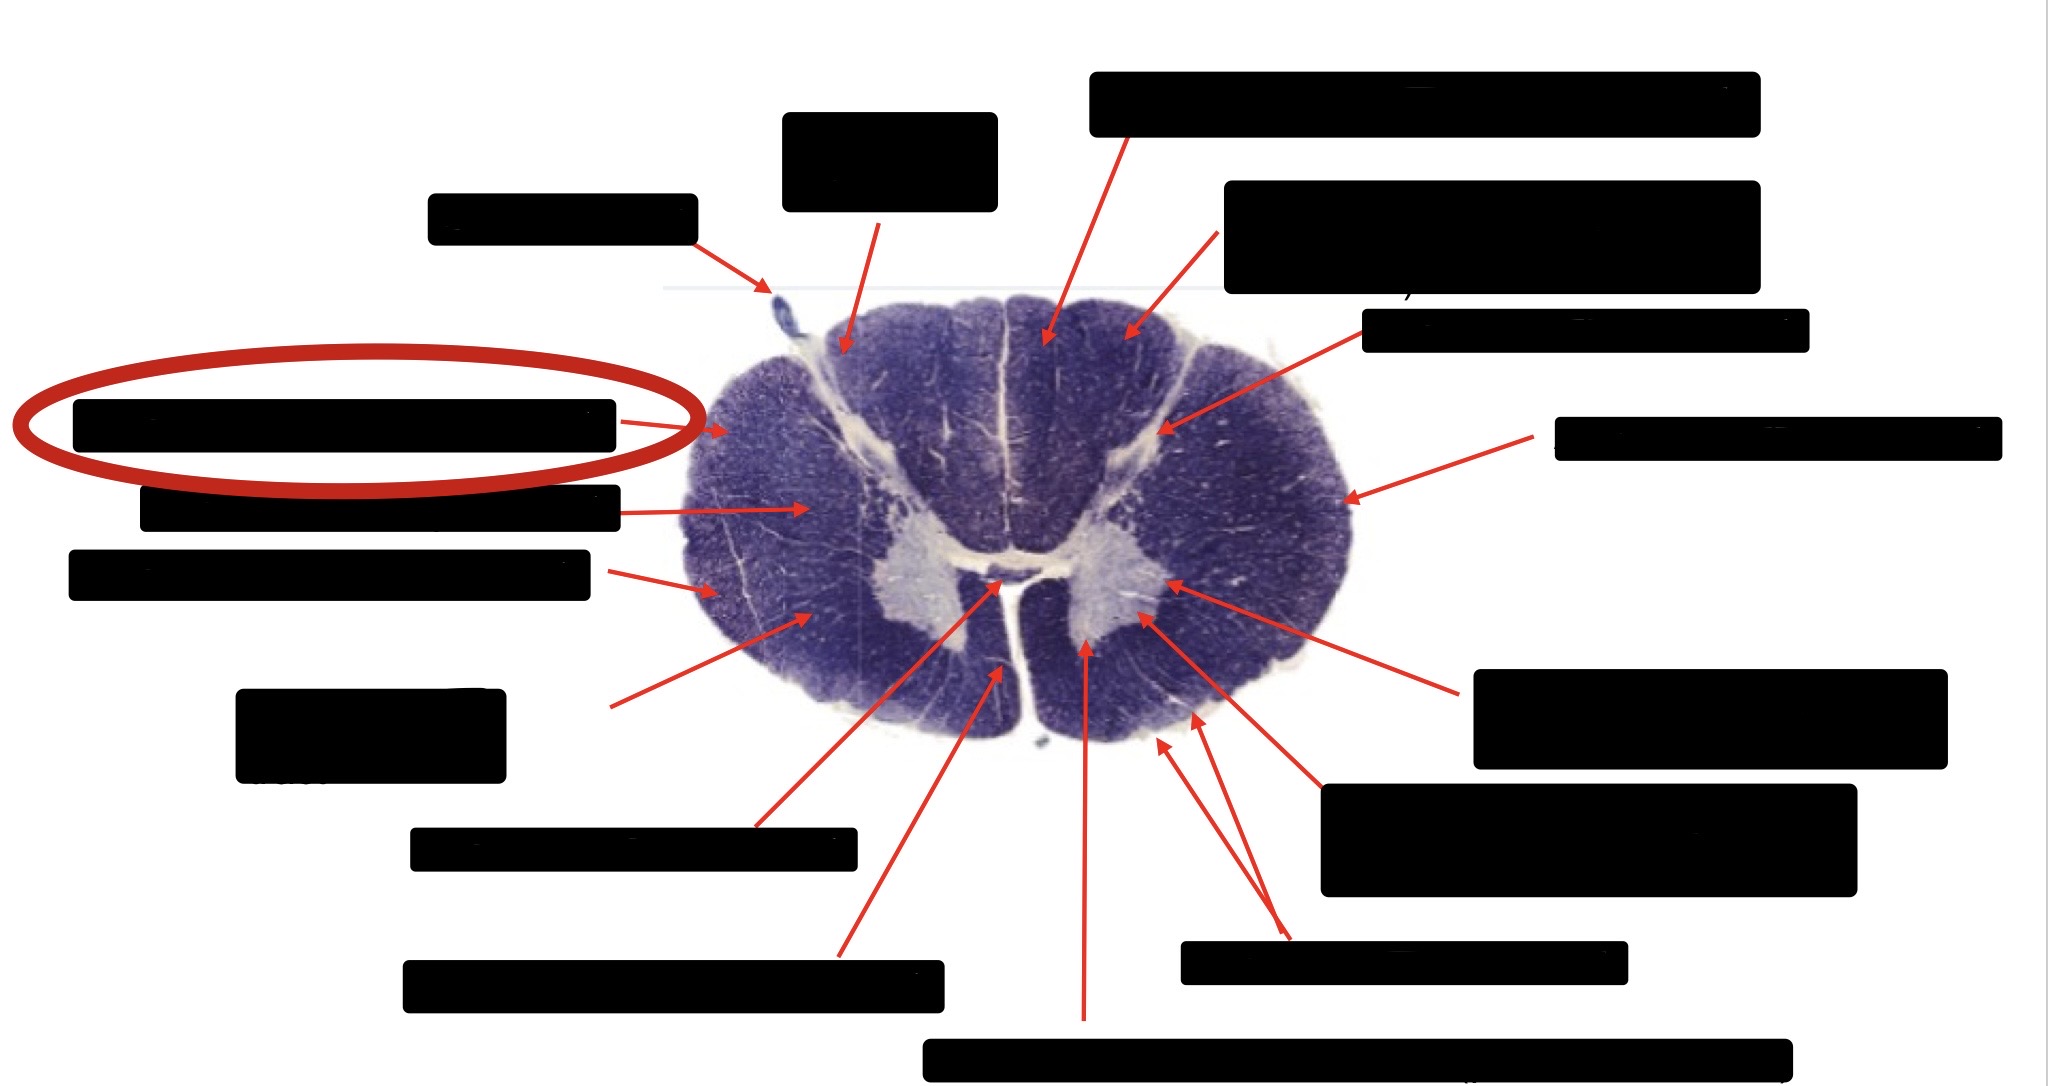

Anterior Spinal Artery

Denticulate Ligament

Ventral Root

Dorsal Root

Posterior Column Fasciculus Gracilis

Large Fiber Entry Zone

Central Canal

Dorsal Rootlet

Lissaeur’s Tract & Small Fiber Entry Zone

Substantia Gelatinosa

Lateral Corticospinal Tract

Anterior Horn Motor Neuron

Spinothalmic Tract

Anterior Horn Motor Neurons